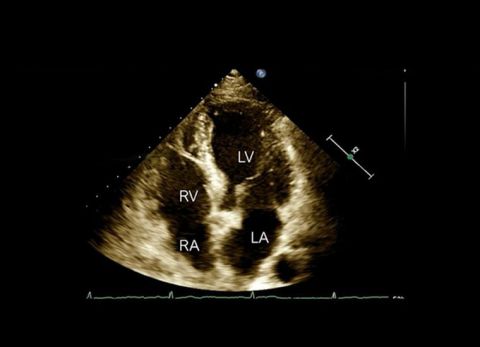

Wideo Echokardiografia. Przypadek 11

prof. dr hab. n. med. Zbigniew GąsiorPacjentka z narastającą od miesięcy dusznością wysiłkową (klasa NYHA III); przewlekła choroba nerek, nadciśnienie tętnicze.